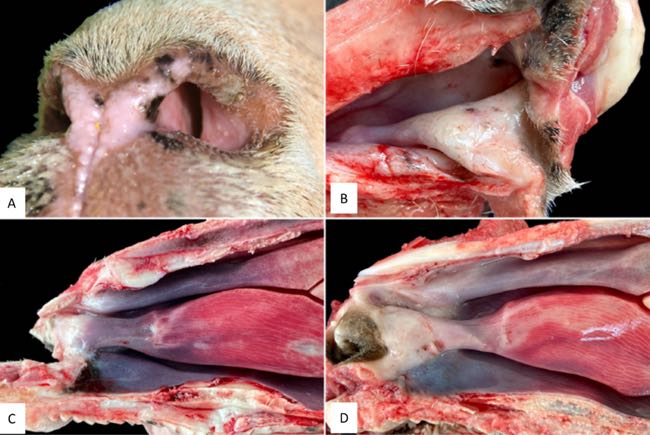

The animals were then humanely euthanised for detailed post-mortem examination of the nasal cavity, liver and pancreas, as well as selected skin sites. Grossly, all sheep showed marked narrowing of the rostral nasal cavity due to proliferation of whitish tissue in the alar folds. The rostral segment of the dorsal nasal turbinate, alar fold, basal fold and adjacent areas of the ventral nasal turbinate were affected with variable caudal extension. The nasal mucosa in these areas was pearl white, slightly raised and patchily roughened, with the most severe lesions at the alar folds, resulting in a marked reduction of airflow (Figure 4).

Figure 4. A. Left nostril of sheep, showing the narrow airway tract due to the presence of a whitish tissue. B. Dorsolateral view of the right nasal cavity. The alar fold and adjacent areas of the nasal mucosa appear thickened with a pearly white colour and have rough surfaces. C. Sagittal section. Gross changes were circumscribed to a small area on the alar fold, with a whitish pearl colour. D. Sagittal section. In this sheep, gross changes were more extensive, affecting from the alar fold to the dorsal, ventral nasal conchae, and ventral fold, all of them with a whitish-pearl colour.